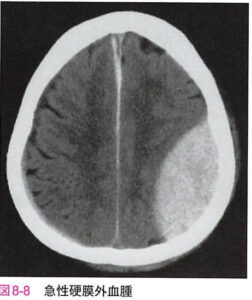

| 急性硬膜外血腫 | 頭蓋骨骨折により硬膜上の硬膜動脈や静脈洞から出血し硬膜外に血腫をつくる。意識清明期があり、CTで凸レンズ型の高吸収が特徴。![]() |

急性硬膜外血腫 Acute epidural hematoma

| 病態 | 頭蓋骨骨折により頭蓋骨と硬膜との間に出血(中硬膜A破綻が約60%と最多)が起こり、脳実質を圧迫する病態。![]() |

| 症状 | ①数時間の意識清明期の後に急激な意識障害(テント切痕ヘルニアによる脳幹圧迫) |

| 検査 | 【画像検査】 頭部CT:骨折部に凸レンズ型の高吸収域(受傷直後は認めないこともある)→骨と骨のつなぎ目以上には広がらないのため凸レンズになるのが特徴 |

| 治療 | 血腫が1cm以上の場合、緊急開頭して開頭血腫除去+出血源止血 |